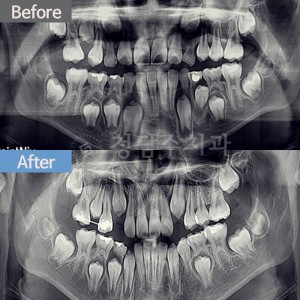

치료전후사진 6 페이지 | 대전청담수치과 - 둔산동치과, 대전치과, 대전교정치과, 대전임플란트